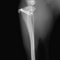

■ 症例20 ポメラニアン 8ヶ月 1.8kg

左右膝蓋骨脱臼 グレードⅢ

2ヶ月前から間欠的跛行が認められ、両膝の膝蓋骨脱臼整復術を行った。

手技は縫工筋及び内側広筋の解放、脛骨粗面の外側転位、滑車ブロック形造溝術、内外側関節包の縫縮を選択し実施した。

右側の膝蓋骨脱臼は上記手技で整復されたものの、左側はそれのみでは膝蓋骨が浮く様子が認められた。その為、PDS縫合糸にて膝蓋靱帯を1糸のみ縫合し、靱帯の縫縮を行った。

膝蓋骨脱臼は膝関節における膝蓋骨の内外側の脱臼と定義されるが、時として単純な内外の脱臼ではなく、膝蓋骨が大きく前方に浮き上がるように脱臼する場合がある。特にトイプードルやポメラニアンといった犬種に多く認められる。

内側脱臼に加えて前方への浮き上がりを矯正する為に、従来より脛骨粗面転移により膝蓋靭帯を外方と下方に引っ張り、固定する方法を選択する。膝蓋骨の前方への浮き上がりが軽度の場合は、従来法ではなく関節包の縫縮で対応していた。しかし、一部の症例で膝蓋骨の動きが悪くなり伸展機構が円滑に機能せずロボット様歩行になるケースがあった。

その為、膝蓋靭帯自体を縫縮する方法を採用した。この方法により、膝関節の伸展機構を妨げず膝蓋骨の軽度の浮きを矯正することが可能となった。

本症例の経過は良好である